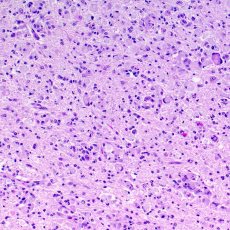

Leukodystrophies are a group of rare genetic disorders that affect the central nervous system (CNS). The CNS is made up of your brain and spinal cord. Leukodystrophies damage the white matter of your CNS. The white matter includes:

- Nerve fibers, also called axons, which connect your nerve cells

- Myelin, a layer of proteins and fatty materials that covers and protects the nerve fibers. It also helps speed up signals between the nerve cells.

When the white matter is damaged, it can slow down or block the signals between nerve cells. This can cause many different symptoms, including trouble with movement, vision, hearing, and thinking.